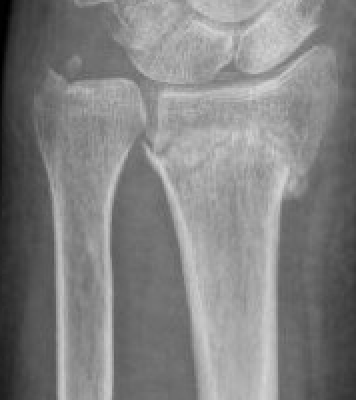

Classification ulna styloid fractures

| Type 1: Tip | Type 2: Base | Type 3: Proximal to styloid |